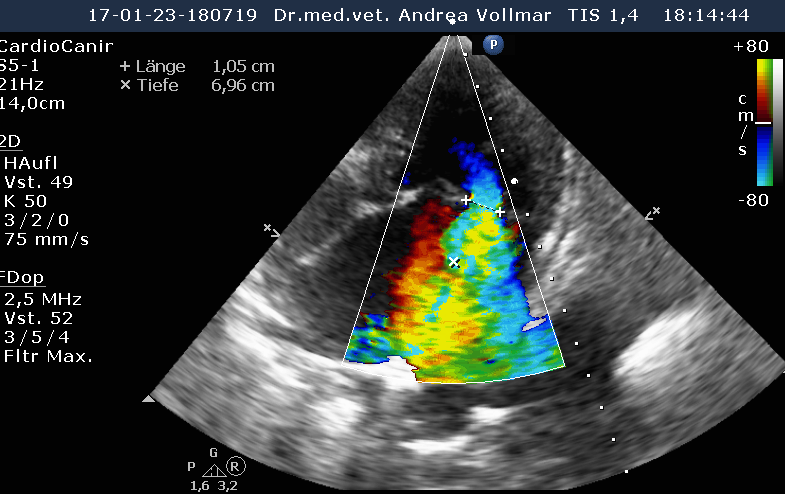

Am sichersten kann die Größe der einzelnen Herzabteilungen und der Schweregrad einer AV-Klappeninsuffizienz mit Hilfe der Echokardiografie beurteilt werden. Die Messung der Vorhofgröße vorzugsweise im 2D-Bild korreliert zuverlässig mit dem Ausmaß der MI. Mittels verschiedener Doppler- und Farbdoppler-Analysemethoden kann die Größe der Lücke in der Mitralklappe bestimmt und das regurgitierte Blutvolumen ermittelt werden.

Liegt eine Trikuspidalklappeninsuffizienz vor, bestimmt man anhand der Geschwindigkeit des Regurgitationsjets den arteriellen Lungendruck. Eine pulmonale arterielle Hypertonie (PAH) kann sich primär (idiopathisch) oder sekundär als Folge chronischer Lungen- oder Herz- und Gefäßerkrankungen entwickeln und beeinträchtigt Lebensqualität, Belastbarkeit und Lebenserwartung. Entsteht als Folge des Lungenhochdrucks eine Rechtsherzinsuffizienz, verschlechtert dies zusätzlich die Prognose.